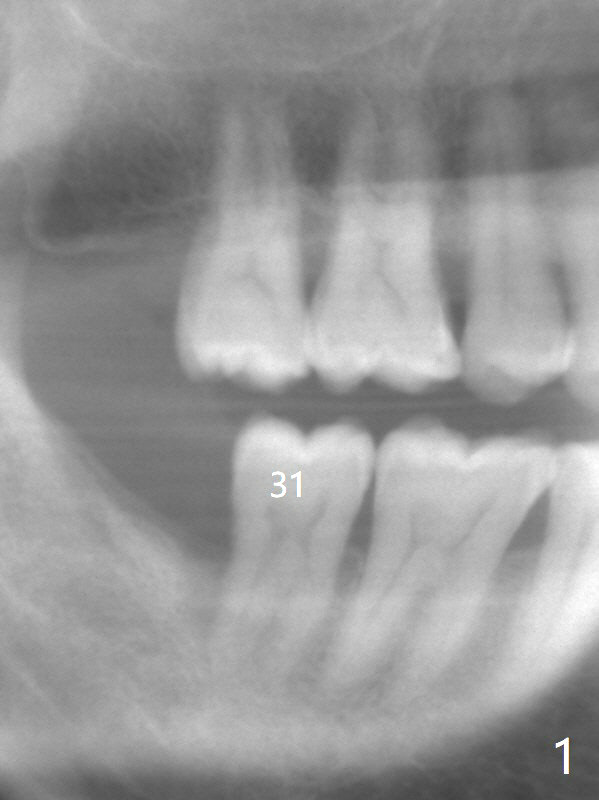

A 62-year-old man does not masticate on the right side due to facial paralysis (Fig.1 (pan taken ~ 8.5 years earlier)). Two years 9 months post #31 extraction, the tooth #2 has supraerupted (Fig.2). Nearly 7 years post extraction of #31 (Fig.3), the patient requests extraction of the supraerupted tooth because of repeated infection (Fig.4 distal view of the extracted tooth). There is calculus in the furca between the palatal (P) and buccal (B) roots. To facilitate bone regeneration in the distal surface of the tooth #3, Osteogen plug is placed in the distal portion of the socket of #2 (Fig.5 O), while allograft in the mesial one (*).